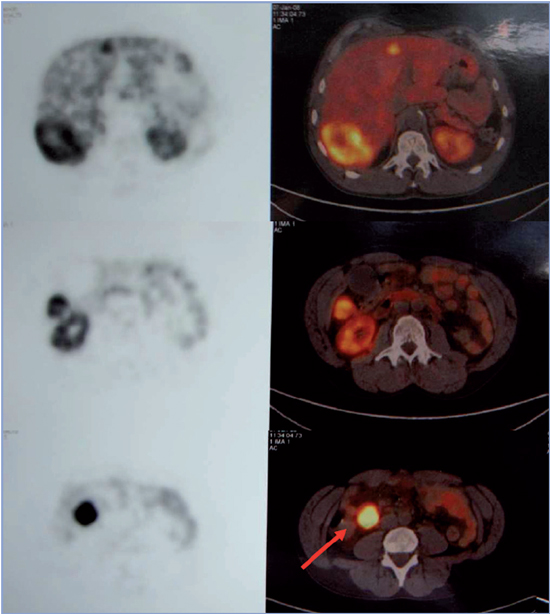

Se realizó Tomografía Computarizada (TC) de abdomen y pelvis con contraste que mostró numerosas lesiones nodulares hepáticas con características de "hemangiomas": una lesión en segmento VII de 9,3 cm, otra en segmento V de 3,5 cm, dos lesiones en segmento II de 3,3 cm y 5,7 cm, y otra en segmento IV de 1,8 cm; además colelitiasis y masa en mesenterio a derecha que comprimía un asa de intestino delgado sin plano de separación, sugerente de neoplasia de intestino delgado (Figura 1).

Figura 1. TC abdominal con contraste que revela la presencia de múltiples lesiones nodulares hepáticas (flechas) y una masa que engruesa el mesenterio y reduce parcialmente el lumen del íleon terminal (punta de flecha).